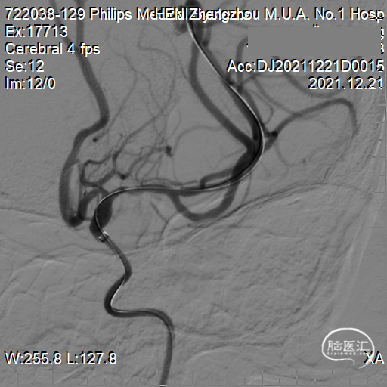

2mm*15mm Gateway球囊到位。

扩张后造影。

球囊扩张后随机Wingspan支架。

支架位置良好狭窄改善明显。